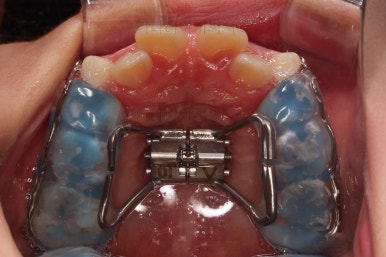

입 안에는 이런 장치가 들어가요.

착탈식은 아니고 부착형입니다.

앞니를 일부러 붕 띄워주며 위턱의 가로폭을 확장시켜주는 악궁확장장치도 부착이 되었어요.

어떻게 식사를 하냐며 걱정하시는 보호자분들이 계시지만 씹는 면을 편평하게 아랫니와 맞춰주었기 때문에 기존의 부정교합인 상태보다 오히려 식사가 잘 될 수 있으니 염려 안하셔도 됩니다.

위턱뼈가 가로로 넓어지니 앞니 사이에도 공간이 많이 생겼네요.